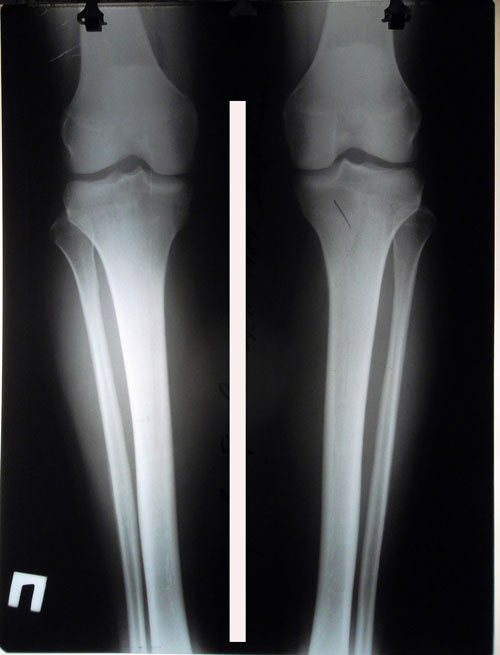

Исходник - 26 лет.

Дата операции 27.09.2016г.